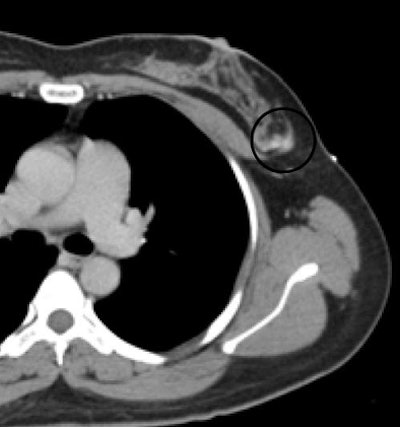

A typical inaccessible lesion found at MR was "a slightly irregular lesion picked up on MR that's at the back of our [biopsy] grid," he said. "That's as far back as we can accurately position a needle, and even if we could put the needle farther forward, we're getting very close to the chest wall." CT visualized the small infiltrating ductal carcinoma, and a hookwire localization biopsy was performed.

![]() |

| Breast lesion (circle) was biopsied using CT guidance. |

CT allows for supine imaging, and the patient can be positioned obliquely. CT also allows for adjunctive ultrasound, an option not possible in the MR suite.